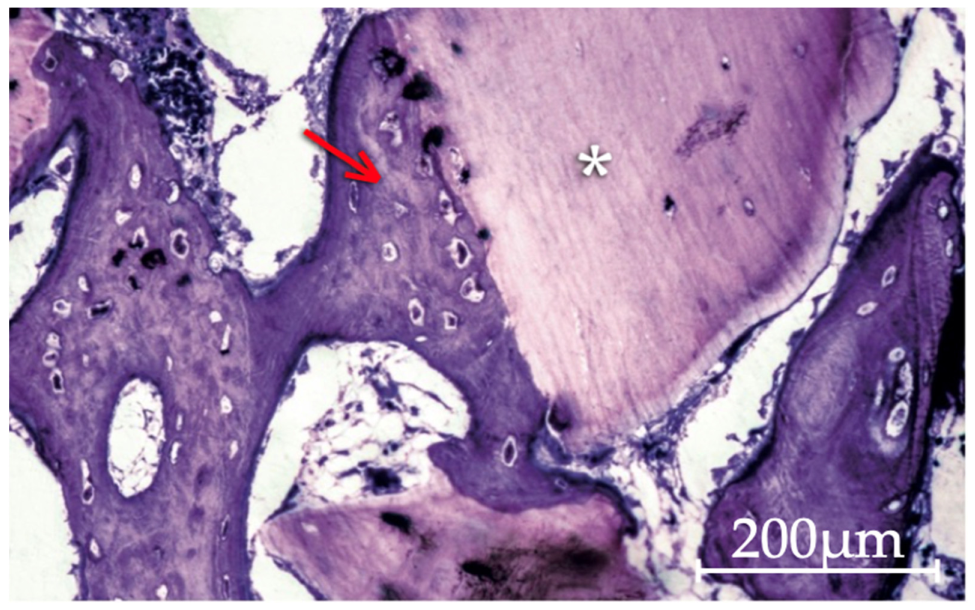

3.2.1. Apatos Group

3.2.2. Gen-Os Group

3.2.3. mp3 Group

3.2.4. Putty and Gel 40 Groups